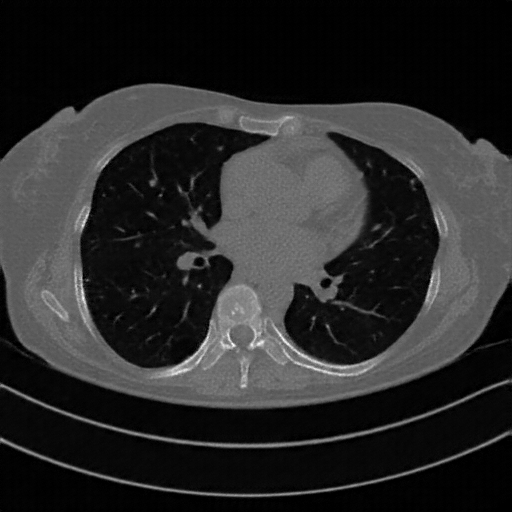

Original VENOUS CT scan

Lung window (WL -600, WW 1500 β†’ Low βˆ’1350, High +150)

Actual HU range: [-1024.0, 150.0]